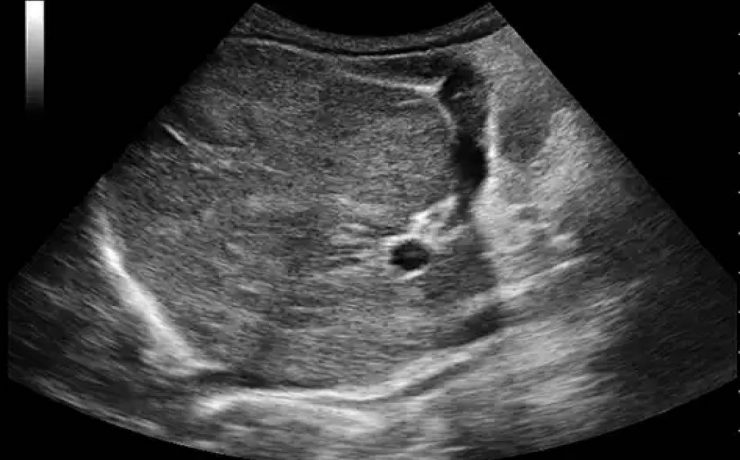

BAZO ACCESORIO SIMULANDO TUMOR SUPRARRENAL

El diagnóstico de los así llamados “incidentalomas” suprarrenales, cada vez más frecuente en la práctica clínica, plantea un diagnóstico diferencial importante. Caso clínico: Se presenta el caso clínico de una paciente de 69 años, hipertensa, con el hallazgo de una masa suprarrenal izquierda aparentemente funcionante, operada por vía laparoscópica y